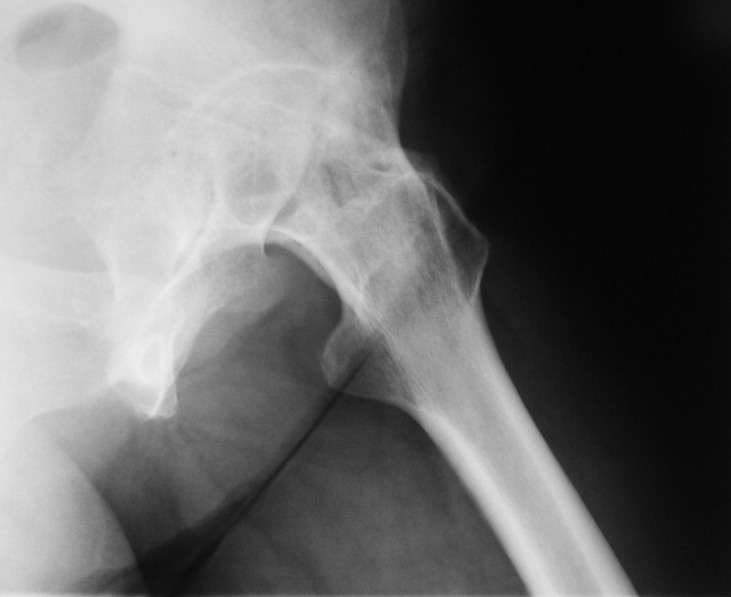

При обследовании выявлен анкилоз тазобедренного сустава в приведении. Видимо, в период пребывания в тяжелом состоянии появились гетеротопические оссификаты. За исключением того, что осталась одна почка, сейчас других медицинских проблем нет.

Пациентку в первую очередь беспокоят боли в спине, на отсутствие движений в суставе она вроде и не жалуется. Вопрос насчет тактики. Корсет и анальгетики вряд ли решение. Первый вариант - удаление оссификатов и эндпротезирование, второй - корригирующая остеотомия в проксимальном отделе с устранением порочного положения.

Второй вариант много проще и менее травматичен. Можно ли без размыкания сустава рассчитывать на существенное уменьшение боли за счет устранения перекоса таза?

Боли в спине обусловлены порочным положением бедра. Эндопротезирование более интересно, т.к. дает еще и движения в суставе (кроме устранения порочного положения). Оссификаты не страшные, а учитывая срок (3 года) - уже созревшие. Я зарекся делать ЭТС при больших оссификатах - очень частый рецидив даже на фоне индометацина и луч.терапии.

Я думаю, что эндопротезирование - более предпочтительный вариант у пациентки 53 лет. К тому же суставная щель прослеживается и, вероятнее, большой сложности с установкой вертлужного компонента не будет. Высока вероятность необходимости аддуктотомии.

В любом случае замена сустава после оссификации дело не благодарное - безболезненная контрактура станет болезненной контрактурой.

После корригирующей остеотомии сохранится чрезмерная нагрузка на поясничный отдел за счёт анкилоза т/бедр. сустава.На фоне остеохондроза,спондилёза,спондилоартроза и спондилолистеза устранение порочного положения не избавит от болей и вряд-ли даже уменьшит их.Мне кажется тут нет альтернативы эндопротезированию.Но даже в этом случае не исключено,что позднее, на повестке появится необходимость вмешательства на позвоночнике.